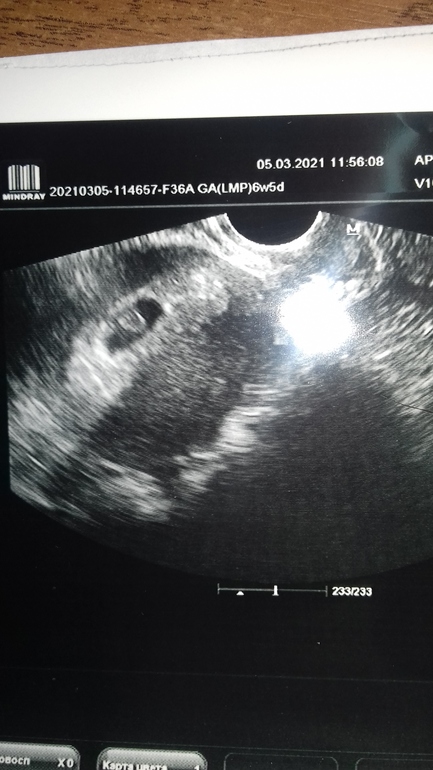

Сегодня, как многие знают, ездила на УЗИ, так как были выделения кровяные...

И заодно нас вновь сфоткали))) Блин так подрос бублик мой за 3 дня☺️

соответствуем своим 6,5 неделям)))

у меня угроза была... и когда увидела, что сердечко бьется.. груз снят был